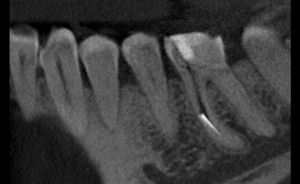

27-latni pacjent zgłosił się do naszej placówki z prośbą o pomoc polegającą na kontynuacji leczenia kanałowego, trwającego już wiele miesięcy. Leczenie przedłużało się z powodu powikłania w postaci złamanego narzędzia endodontycznego, które uniemożliwiało dezynfekcję systemu kanałowego na całej długości. Dodatkową trudnością była lokalizacja narzędzia w połowie długości korzenia za krzywizną kanału, co uniemożliwiało jego widoczność w mikroskopie. Podjęto próbę ominięcia („by passa”) narzędzia, co niestety nie powiodło się. Nieocenioną pomocą w tym precyzyjnym zabiegu okazała się tomografia wolumetryczna, która „sięgała, gdzie wzrok nie sięgał” i ułatwiła bezpieczne usunięcie narzędzia, a następnie pełną dezynfekcję i szczelne wypełnienie systemu korzeniowego. Zabieg trwał 4 godziny (2 wizyty po 2 godziny) i dzięki olbrzymiej cierpliwości pacjenta i precyzji operatora zakończył się sukcesem.